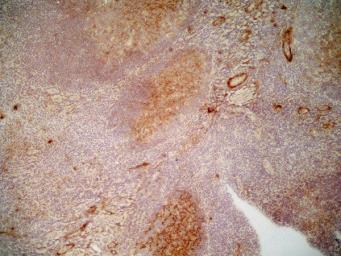

cd36 antibody 11378-1-ap pview

图片尺寸1024x681